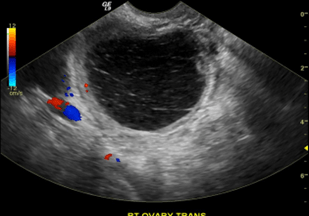

Transvaginal Ultrasound (TVUS)

Transvaginal ultrasound is the gold standard initial imaging modality for evaluating ovarian cystic masses.

Suspicious or Malignant Features

• Solid areas or papillary projections

• Thick septations (3 mm)

• Irregular cyst walls

• Internal vascularity